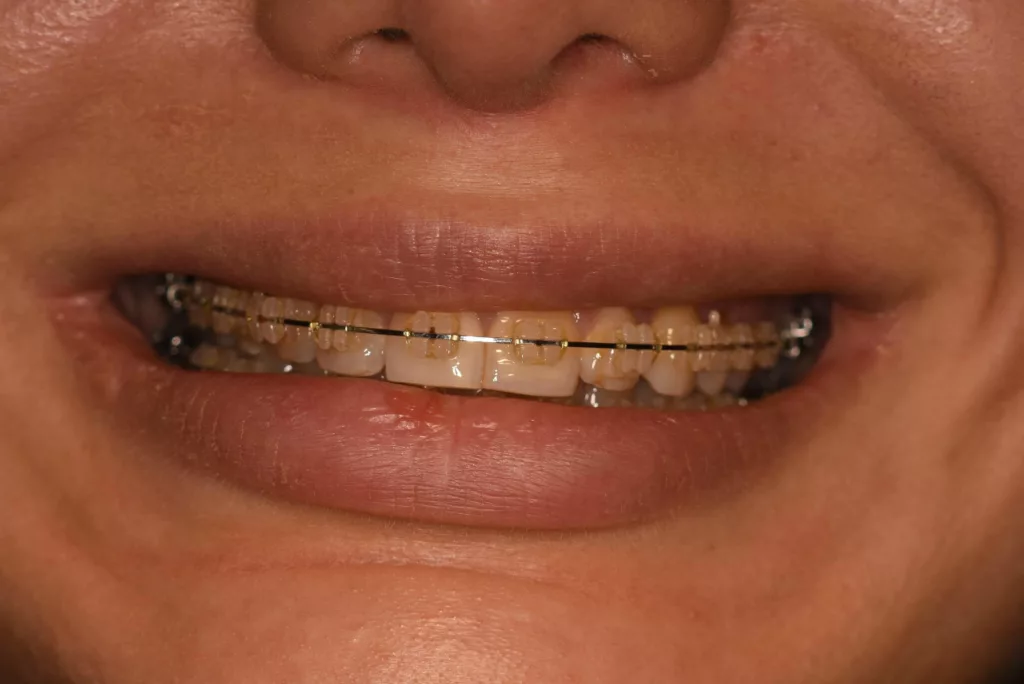

L’orthodontie postchirurgicale

Elle vise à corriger les dernières imperfections de l’articulé dentaire après la chirurgie. « Une contention » consistant en un très fin fil de métal ou de kevlar, est disposée, invisible, sur la face postérieure des dents dans le but de conserver la qualité du résultat occlusal obtenu par l’orthodontie et la chirurgie